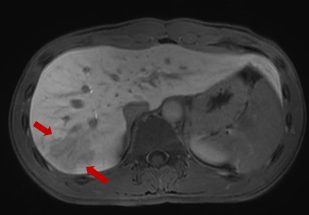

随后,入院查血常规提示嗜酸性粒细胞百分比大于40%,转氨酶明显升高,CT检查提示肝右叶占位性病变。上腹部磁共振增强提示肝右叶包膜下多发液性信号。肥大反应提示丙型副伤寒1:320,考虑沙门菌感染,这是一种由沙门氏菌属细菌引起的常见食源性疾病,可以通过受污染的食物或水传播。

磁共振显示:肝右叶包膜下见多处团片状、楔形病灶。